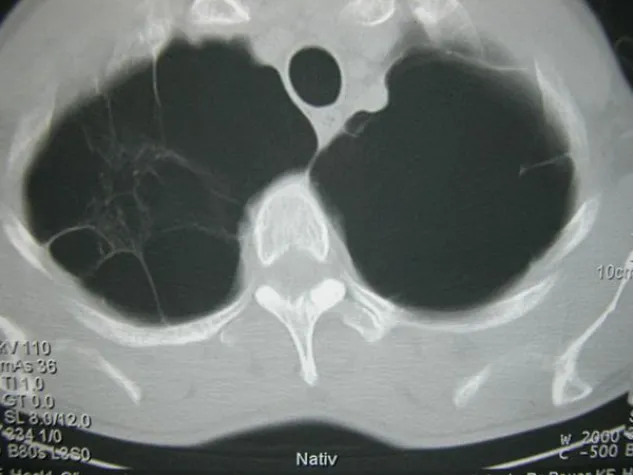

In der von der EU geförderten EvA-Studie haben sich die Wissenschaftler zum Ziel gesetzt, neue genetische Marker für die zwei großen Subtypen der COPD zu identifizieren: das Emphysem und die Verengung der Atemwege (Emphysema versus Airway disease). Viele Patienten weisen beide Krankheiten auf, doch es gibt auch sehr unterschiedliche Ausprägungen. Alle werden unter dem Sammelbegriff COPD zusammengefasst. „Erkenntnisse über den Einfluss der Gene auf die Entstehung der beiden Krankheitsformen verbessert einerseits das Wissen über die Entstehungsmechanismen und bietet andererseits Möglichkeiten für neue Diagnose- und Therapieansätze“, erklärt Prof. Loems Ziegler-Heitbrock vom HelmholtzZentrum München, Koordinator der EvA-Studie. In einer anderen Studie (Nature Genetics, 43: 1082, 2011) hat ein internationales Konsortium 16 neue Regionen im menschlichen Erbgut identifiziert, die Einfluss auf die Lungenfunktion haben. „Ob diese Regionen im Genom für die COPD relevant sind, wissen wir noch nicht. Doch genau das möchten wir mit unserer Studie herausfinden“, so Prof. Ziegler-Heitbrock weiter.

Die Ursache für die Entwicklung der COPD sind chronische Entzündungsprozesse in der Lunge, die vor allem durch das Rauchen ausgelöst werden. Das Fortbestehen der Entzündung führt nach und nach zu einer Verengung von Atemwegen und zu einer Zerstörung des Lungengewebes und damit in mehreren Schritten zu einer Verkleinerung der Oberfläche für den Gasaustausch. Die COPD ist eine Herausforderung für die Gesundheitssysteme, weil sie im Verlauf vieler Jahre hohe Kosten verursacht. Sie führt zu Arbeitsausfällen auf Grund von Krankheitsschüben und zu frühzeitiger Arbeitsunfähigkeit.